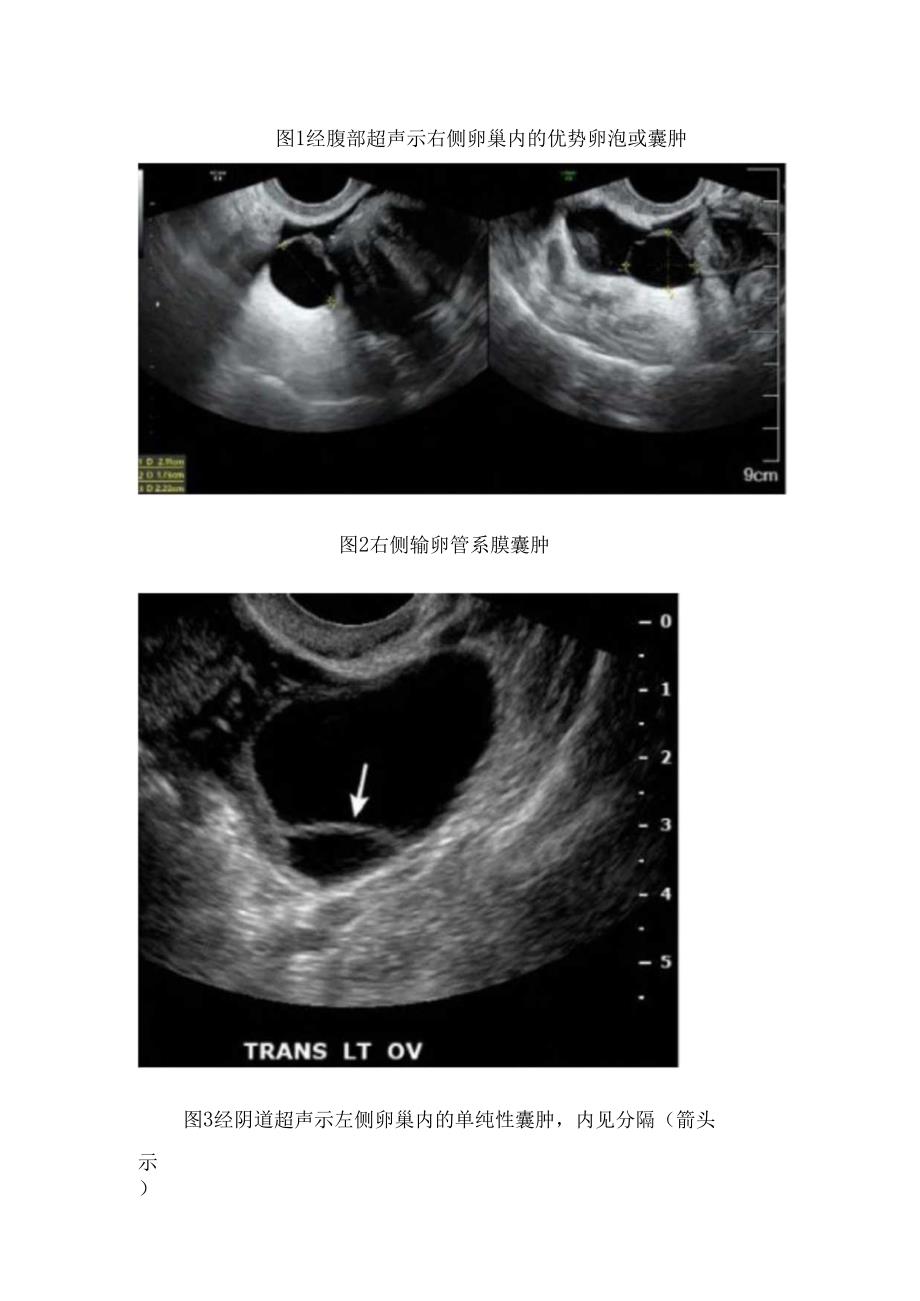

1、临床单纯性囊肿病理、超声表现及鉴别诊断单纯性囊肿在临床上常代表一组组织学相似的附件囊肿。卵泡囊肿、黄体囊肿和附件炎性小囊病变时间较长时,因囊壁纤维化,上皮萎缩和退化,病理表现相似,难辨来源;另外在女性生殖器发育过程中,各部位均有可能出现囊性变,包括输卵管囊肿、圆韧带囊肿以及卵巢冠囊肿、阔韧带囊肿等,一般根据部位来命名或通称为单纯性囊肿。常无任何临床表现。超声表现单纯性囊肿的特征是:呈圆形或椭圆形(图1);可为单侧或双侧,可单囊或多囊同时存在;内为无回声(图2);壁薄,内部可有细而光滑的分隔(图3);一般大小不超过5cmo较大的单纯性囊肿难以扫查到正常卵巢结构,不能判断来源,可仅提示单纯性囊肿;

2、彩色多普勒超声显示囊肿内无血流,囊壁上可见少许血流(图4)。图1经腹部超声示右侧卵巢内的优势卵泡或囊肿图2右侧输卵管系膜囊肿图3经阴道超声示左侧卵巢内的单纯性囊肿,内见分隔(箭头示)图4彩色多普勒超声显示卵巢单纯性囊肿内无血流,囊壁上可见少许血流鉴别诊断卵泡囊肿(follicularcyst)为卵泡成熟后不破裂,或发生闭锁,卵泡腔内液体潴留而形成,一般直径不超过4cm。偶尔可达7-8cmo一般无任何症状和体征,可在逐渐吸收或自行破裂。另外如果看到单纯性囊肿内的卵丘且与月经周期相符合时,考虑为卵泡。黄体囊肿(CorPUSIuteumcyst)见本专题第四节。卵巢冠囊肿(parovariancyst)位于输卵管余卵巢门的两叶阔韧带之间的输卵管系膜内,囊肿由卵巢冠远侧盲端扩大形成,卵巢正常,输卵管被拉长紧靠囊壁。囊肿圆形或类圆形,直径常在5cm左右。